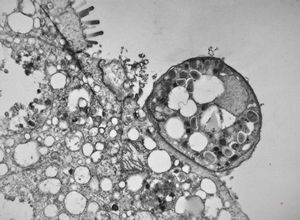

M,3m. | Pneumocystis carinii

M,33y. | cryptosporidiosis - duodenum, im | munodeficient pacient, HE and toluidine blue staining